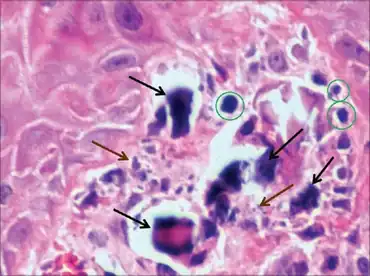

| Histologic sample of subepidermal calcified nodule | |

Subepidermal calcified nodule is a type of Calcinosis cutis. It's a cutaneous condition characterized by calcification of the skin resulting from the deposition of calcium and phosphorus, occurring most frequently as one or a few skin lesions on the scalp or face of children.[2]: 528 Lesions may also appear on the ear and eyelid.